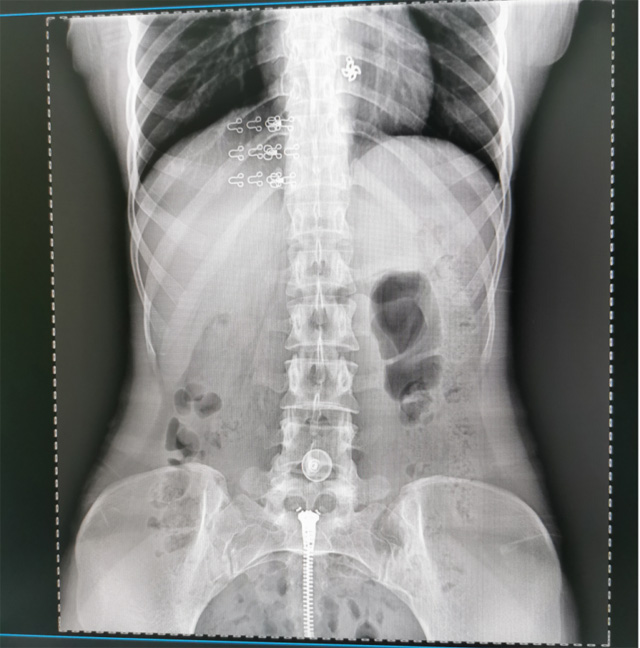

懸吊DR數(shù)字化攝影圖像質(zhì)量高輻射量少誤差小滿足疾病的臨床診斷

提高醫(yī)院的影像科的醫(yī)療服務(wù)水平,滿足滿足人民群眾不斷增長(zhǎng)的醫(yī)療需求,促進(jìn)醫(yī)療技術(shù)快速發(fā)展。醫(yī)院都引進(jìn)懸吊DR拍片設(shè)備新一代數(shù)字化X線攝影系統(tǒng)。標(biāo)志著醫(yī)院的診療水平又上升一個(gè)新的臺(tái)階。懸吊DR滿足人體頭部、胸部、腹部、腰椎、四肢等部位的數(shù)字?jǐn)z影檢查,可以檢查呼吸系統(tǒng)疾病,心臟系統(tǒng)的疾病、骨關(guān)節(jié)系統(tǒng)的疾病,子宮輸卵管造影、胃腸道造影,.有職業(yè)病體檢篩查塵肺病功能。通過(guò)DR數(shù)字化攝影,分段連續(xù)、重疊采集數(shù)字化圖像,利用軟件對(duì)圖像進(jìn)行拼接的方式來(lái)獲得全脊柱、全上肢或全下肢的圖像。新設(shè)備的圖像更清晰,臨床拍攝避免患者再次搬運(yùn)和移動(dòng)產(chǎn)生的痛苦,是創(chuàng)傷骨折患者的福音。輻射減少受照劑量50%,后處理能力強(qiáng)、圖像質(zhì)量高。有效降低操作難度,縮短工作流程,尤其適合大批量體檢。

具有射線劑量小、圖像清晰度高、誤差小等特點(diǎn),懸吊DR已廣泛應(yīng)用于各級(jí)醫(yī)療機(jī)構(gòu)的體檢中心,越來(lái)越受到臨床醫(yī)生的肯定和患者的青睞。為臨床診斷工作提供更加直觀有效的技術(shù)支持,大大提高了患者就醫(yī)效率從而為患者提供更加優(yōu)質(zhì)的醫(yī)療服務(wù)。提高了其成像質(zhì)量和臨床應(yīng)用價(jià)值,并極大減少了受照輻射劑量。有效滿足了各種常見(jiàn)疾病的臨床診斷和治療需求。以醫(yī)療質(zhì)量為根本,以優(yōu)質(zhì)服務(wù)為導(dǎo)向,竭誠(chéng)為人民群眾的健康保駕護(hù)航。